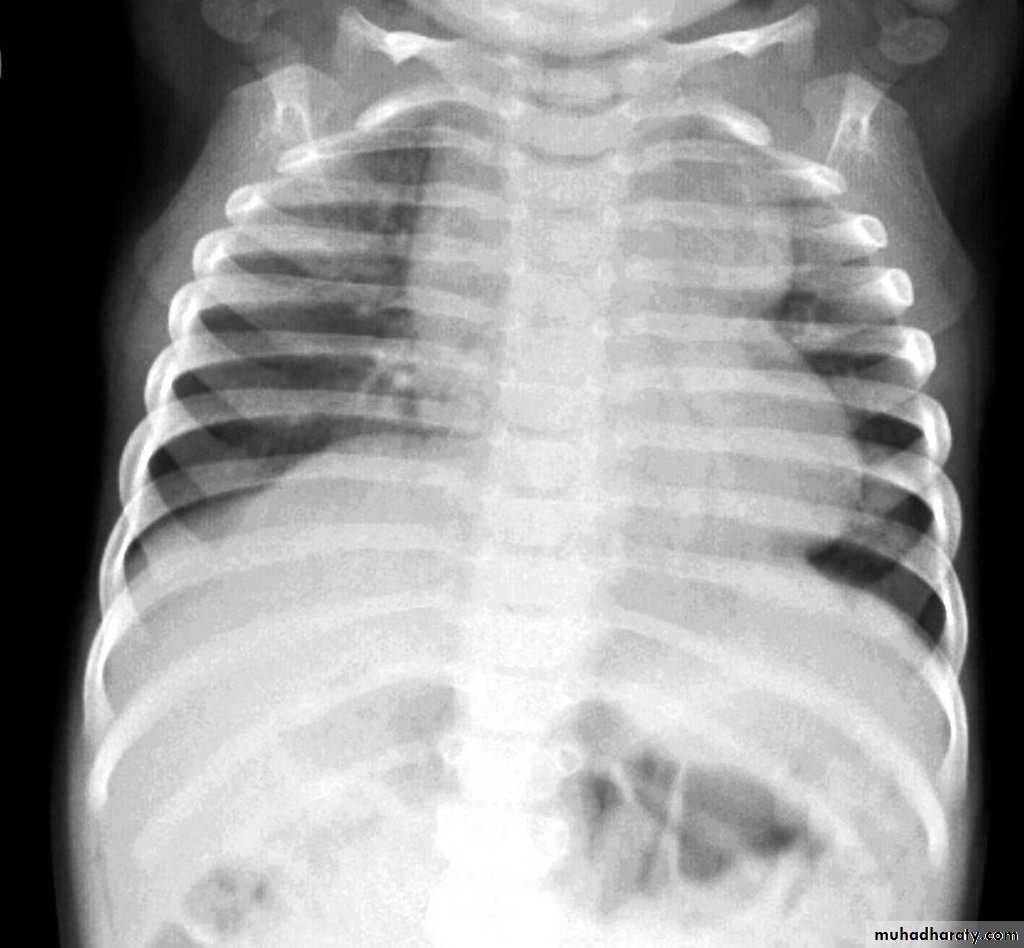

Tetralogy of Fallot (TOF) is one of the most common cyanotic congenital heart conditions and continues to be a major source of morbidity .

Tetralogy of Fallot is classically characterised by four features which are:

ventricular septal defect (VSD) 6

right ventricular outflow tract obstruction (RVOTO) due to:pulmonary artery stenosis

overriding aorta

right ventricular hypertrophy

Radiographic features

Plain film

Plain films may classically show :

1. "boot shaped" heart with an upturned cardiac apex due to right ventricular hypertrophy and concave pulmonary arterial segment.

2.Pulmonary oligaemia due to decreased pulmonary arterial flow.

3.Right sided aortic arch is seen in 25%.

"boot shaped" heart ( TOF )

TOF